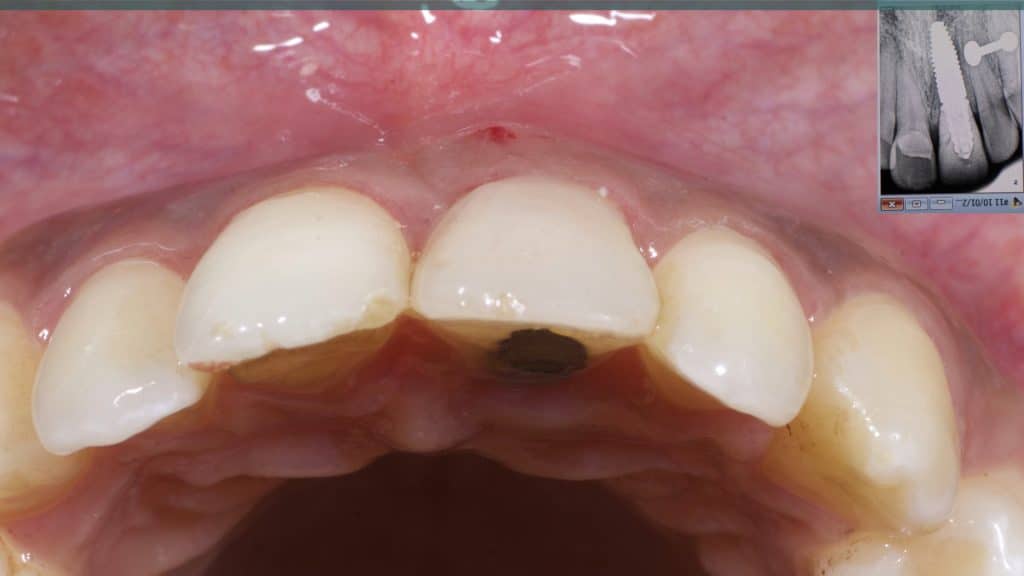

A 27-year female patient with dislodged Resin bonded FPD. She had that FPD for past few years, it had metal wings on palatal surfaces of UR1 and UL2 and a post like metal extension into the root canal of UL1. There was gingival abscess due to fractured root segment most probably due to extended metallic post like structure. Immediate implant placement (IIP) and Immediate restoration (IR) was planned for this patient.

Occlusal check